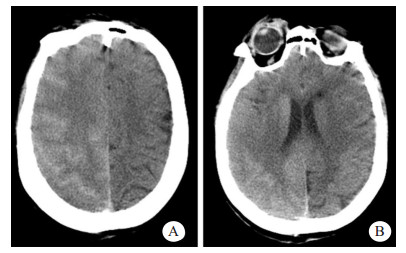

患者女性,71岁,2011年3月行食管癌切除术,6年来反复出现咯血症状,每次均在止血及抗感染治疗后好转。2018年1月20日患者再次出现咯血,入苏州大学附属第二医院介入科治疗。CT检查提示支气管扩张伴感染,遂于2018年1月25日在本院行支气管动脉栓塞术,分别对右支气管动脉远端、支气管动脉主干及左侧肋间动脉进行栓塞,术中使用的造影剂为碘海醇150 mL(浓度为30 g/100 mL)。术后仍出现反复痰中带血,因症状逐渐加重,患者于2018年8月13日再次来本院就诊。患者既往无高血压、糖尿病、心脏病等慢性病病史。入院后,给予患者头孢匹胺抗感染及止血、抑酸等对症支持治疗,咯血症状明显缓解。为进一步明确患者支气管动脉情况并予以处理,于8月17日穿刺右股动脉对患者施行支气管动脉造影+栓塞术,造影显示左侧两支支气管动脉与肋间动脉共干,左侧一支气管动脉血管明显增粗,紊乱,可见小片状可疑出血染色,遂对左侧两支与肋间动脉共干的支气管动脉分别予以栓塞,术中使用的造影剂为碘海醇100 mL(浓度为30 g/100 mL)。术中患者未有不适,术后患者安返病房。术后2 h, 患者无明显诱因下突然出现谵妄,查体:T 36.6℃,P 110次/min,BP 190/80 mmHg (1 mmHg=0.133 kPa),双侧瞳孔对光反射存在,左上肢肌力1级,右上肢肌力5级。急诊颅脑CT显示,右侧脑沟裂、纵裂池密度增高,局部脑实质肿胀、密度增高(图 1)。术后4 h颅脑MRI显示,右侧额叶部分皮质增厚,皮质T1WI信号稍减低,T2WI、T2WI-FLAIR、DWI信号增高,ADC信号稍高;右侧放射冠区见斑片状T1WI稍低信号,T2WI、T2WI-FLAIR、DWI高信号,ADC稍高信号影(图 2A~E);颅脑与颈部TOF-MRA显示各动脉未见明显扩张或狭窄征象。结合患者临床及影像学表现,在排除心脑血管病变后,经多学科会诊,考虑造影剂脑病。给予患者糖皮质激素抗炎、甘露醇降颅压、改善微循环及纠正电解质紊乱等对症处理,患者于术后第3天意识恢复,左侧肢体肌力明显好转。术后第6天,患者精神状态与左侧肢体肌力完全恢复,复查颅脑CT显示脑沟裂池内及局部脑实质高密度影消失,MRI各序列(图 2F~J)未见明显异常,予以出院,随访至今,患者未有不适。

| 患者介入栓塞术后4 h(A~E),示右侧额叶部分皮质增厚,皮质T1WI信稍稍减低,T2WI、T2WI-FLAIR、DWI信号增高,ADC信号稍高;右侧放射冠区见斑片状T1WI稍低信号,T2WI、T2WI-FLAIR、DWI高信号,ADC稍高信号影。患者出现症状后第6天复查(F~J)示颅脑已基本显示正常 图 2 患者颅脑MRI检查结果 |